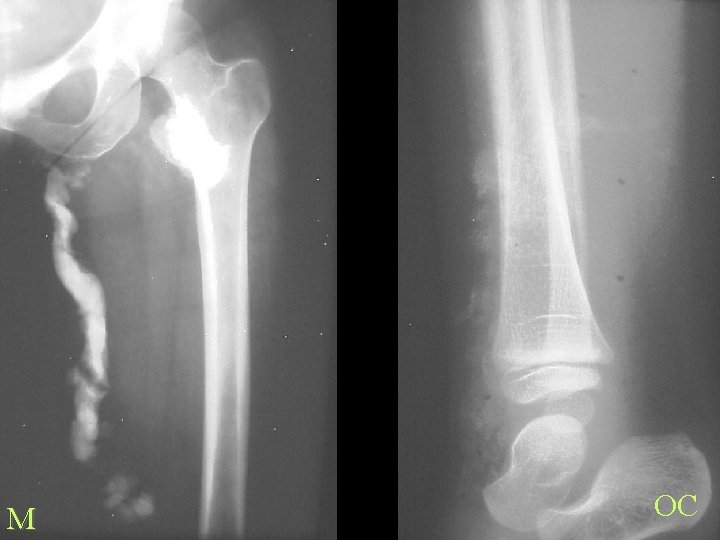

M OC